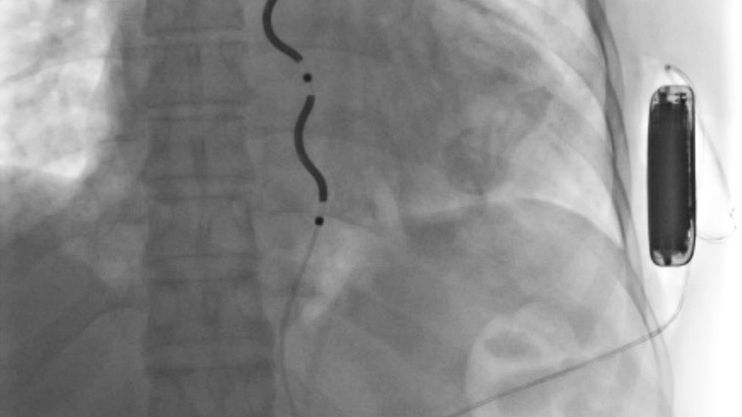

EV-ICD składa się z elektrody oraz generatora impulsów. Jego zadaniem jest wykrycie niebezpiecznej arytmii i natychmiastowe przerwanie jej za pomocą impulsu elektrycznego, zanim dojdzie do poważnych, nieodwracalnych zmian w organizmie. W odróżnieniu od tradycyjnych defibrylatorów, w których elektroda wprowadzana jest przez żyły bezpośrednio do wnętrza serca, w nowym rozwiązaniu elektroda znajduje się pod mostkiem, a generator umieszczany jest pod skórą w okolicy lewej pachy.

Pierwszym pacjentem, który skorzystał z nowej technologii w Poznaniu, był 47-letni mężczyzna po wielokrotnych zatrzymaniach krążenia. Po skutecznej reanimacji w karetce i na szpitalnym oddziale ratunkowym oraz po wykluczeniu odwracalnych przyczyn arytmii, zakwalifikowano go do innowacyjnego zabiegu. Operację wykonano 15 lipca, po wcześniejszym przygotowaniu obejmującym szczegółowe badania obrazowe, znieczulenie ogólne i test skuteczności defibrylacji. Wszczepienia dokonali lekarze z Oddziału Kardiologicznego – lek. Michał Guliński i dr n. med. Andrzej Bolewski oraz z Oddziału Kardiochirurgicznego dr n. med. Karol Buszkiewicz i lek. Roman Olszewski.